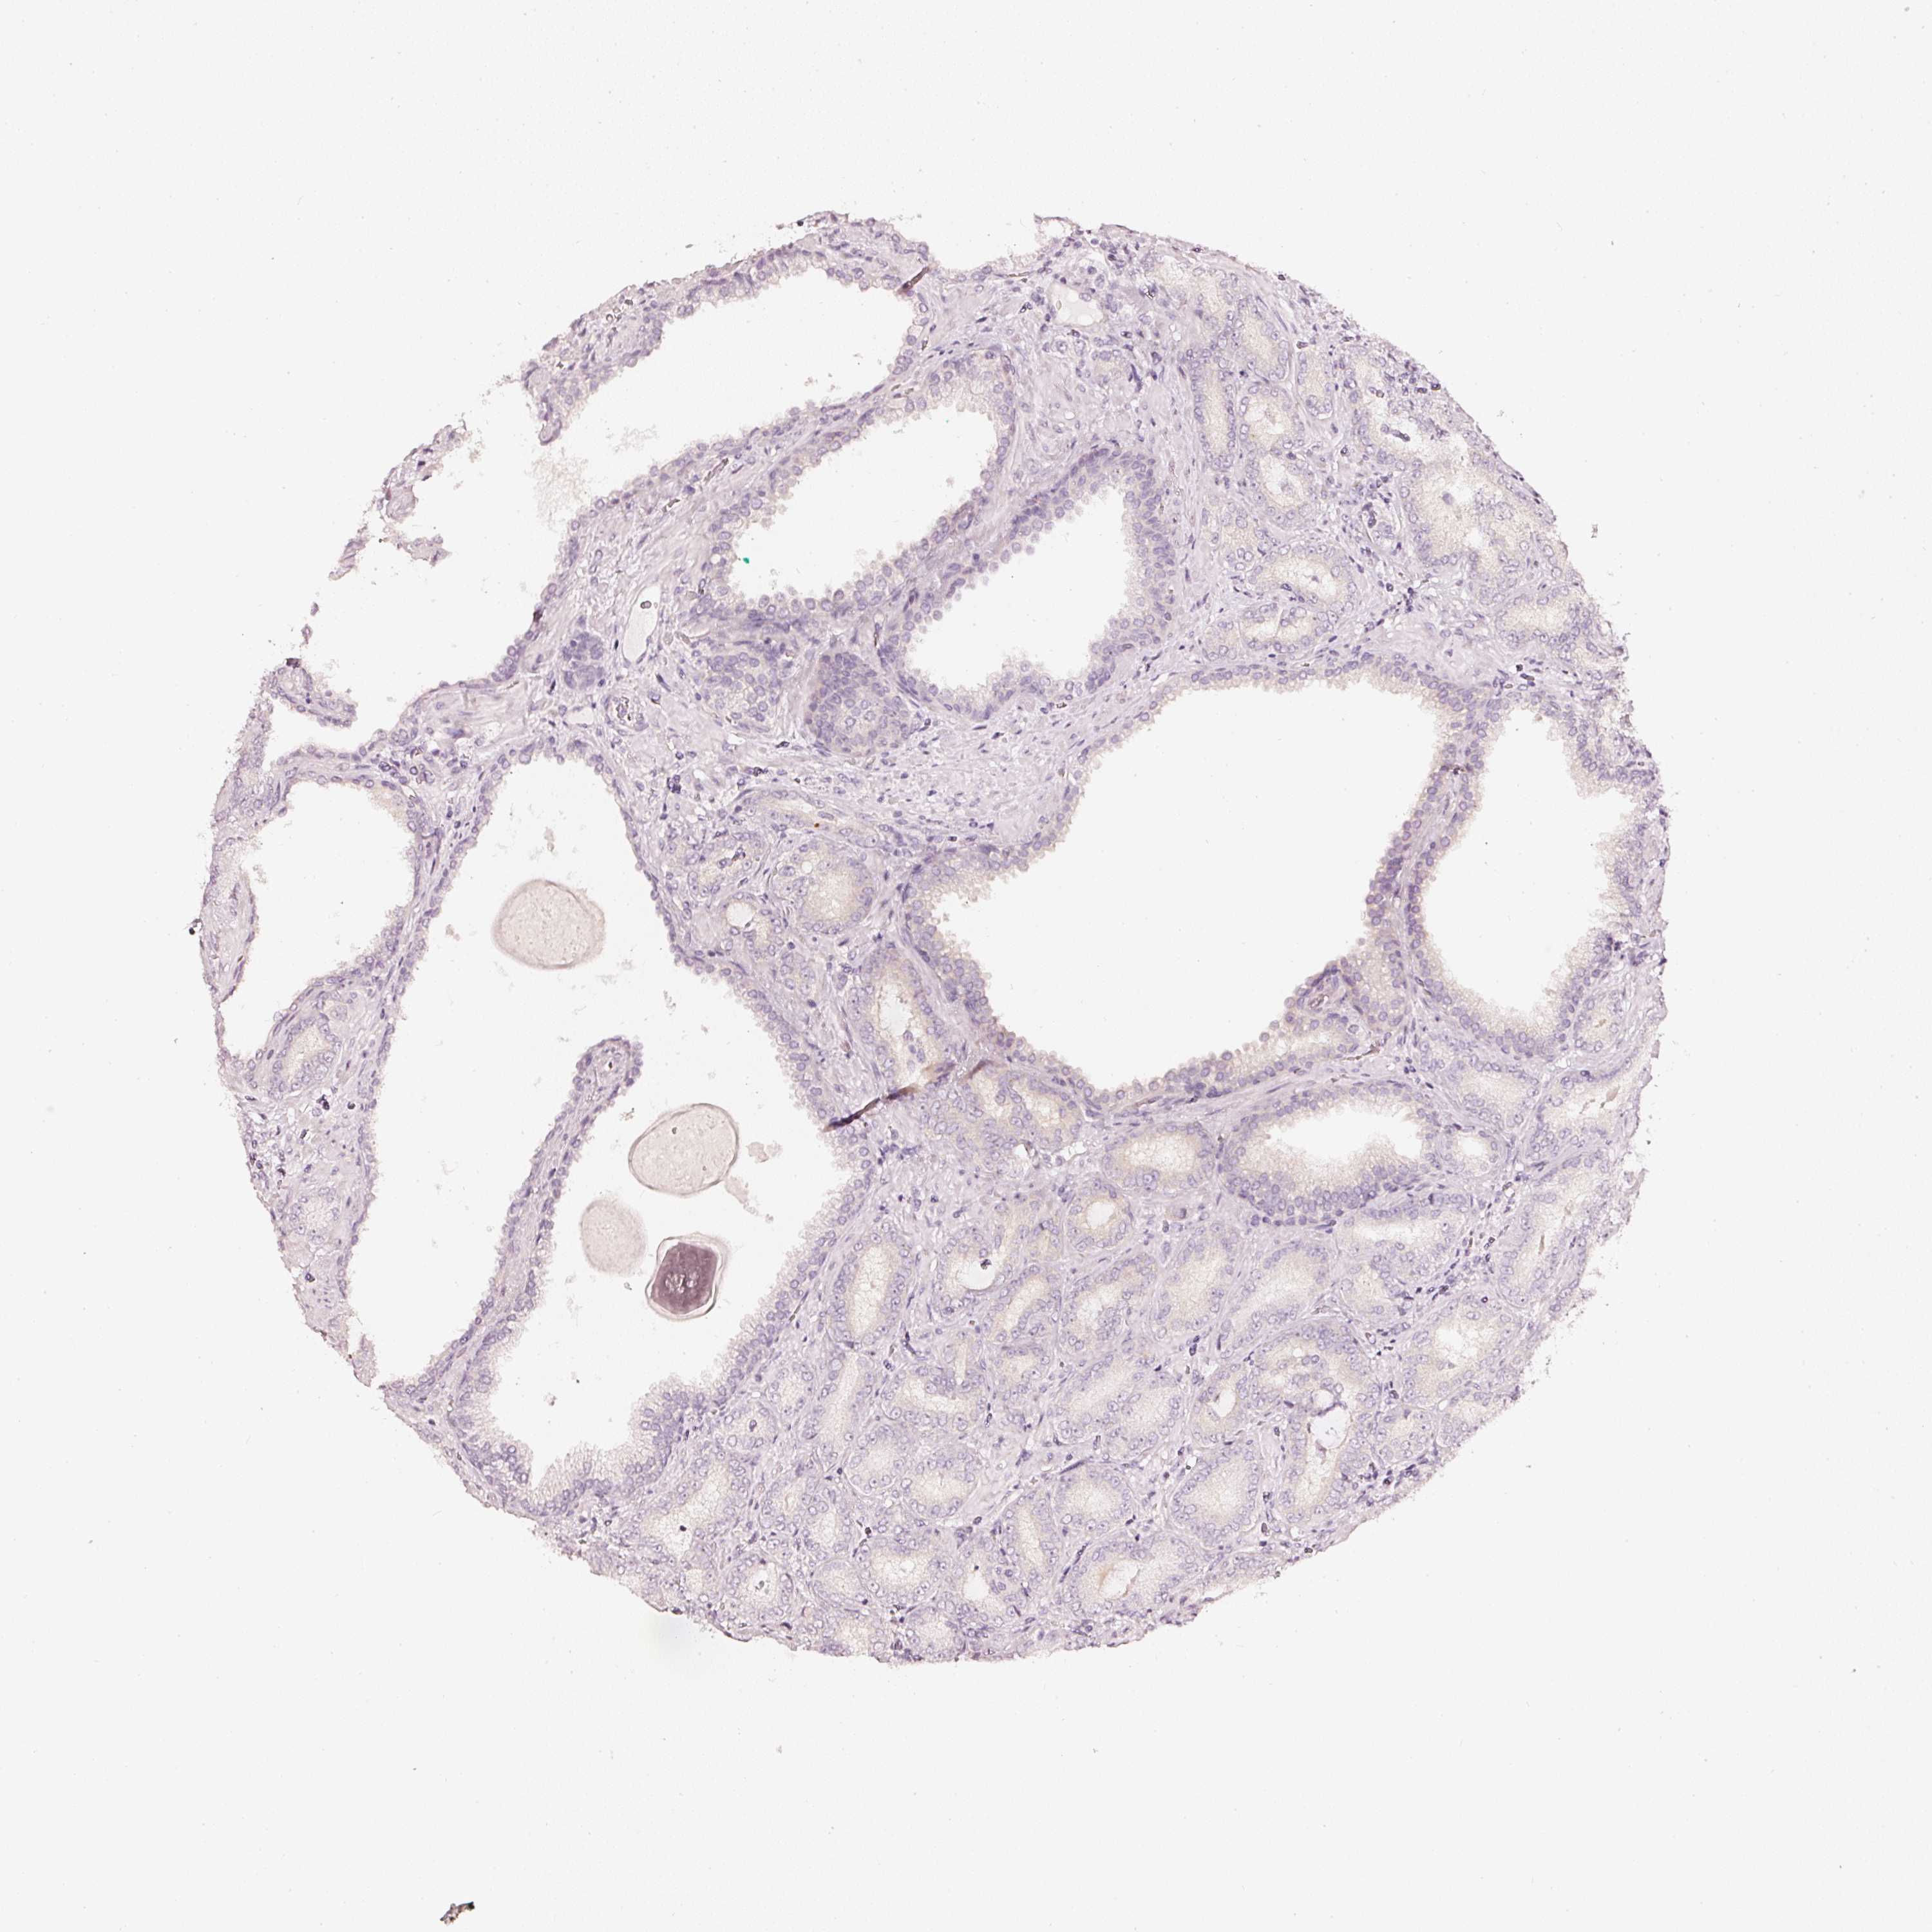

PROSTATE CANCER - Protein expressioni

A mouse-over function shows sample information and annotation data. Click on an image to view it in a full screen mode. Samples can be filtered based on level of antibody staining by selecting one or several of the following categories: high, medium, low and not detected. The assay and annotation is described here.

Note that samples used for immunohistochemistry by the Human Protein Atlas do not correspond to samples in the TCGA dataset.

Antibody stainingi

Antibody staining in the annotated cell types in the current human tissue is reported as not detected, low, medium, or high, based on conventional immunohistochemistry profiling in selected tissues. This score is based on the combination of the staining intensity and fraction of stained cells.

Each image is clickable and will lead to virtual microscopy that enables deeper exploration of all samples and also displays staining intensity scores, fraction scores and subcellular localization as well as patient and tissue information for each sample.

Adenocarcinoma, High grade

Adenocarcinoma, Low grade

Adenocarcinoma, NOS

Adenocarcinoma, Medium grade